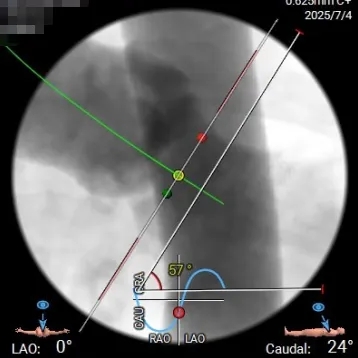

投照体位及瓣环角度分析

Angio

右窦中心

左右重合

右无重合-左冠切线位